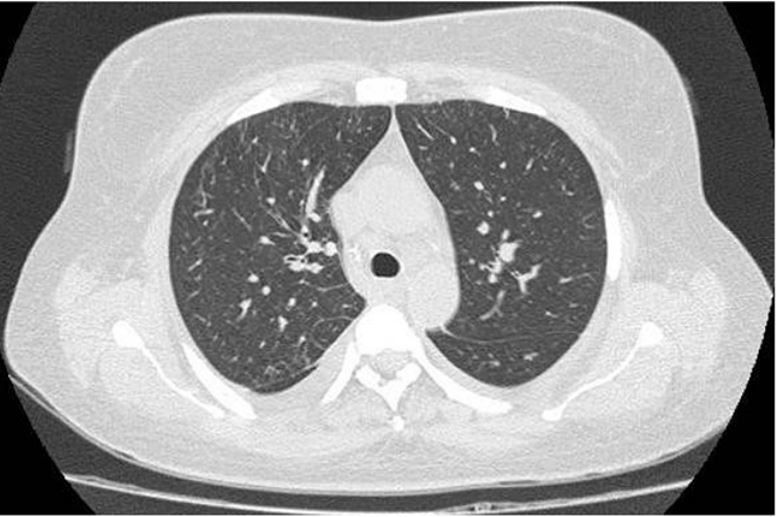

La tomografía de tórax mostró áreas extensas confluyentes de vidrio esmerilado bilaterales difusas (figura 1). Dada la impresión diagnóstica de neumonía grave, se inició oxigenoterapia y antibioticoterapia de amplio espectro (piperacilina/tazobactam de 4,5 g cada 6 horas; vancomicina de 1 g cada día; trimetoprima/sulfametoxazol de 800/160 cada 8 horas; claritromicina de 500 mg vía oral cada 12 horas, y oseltamivir de 75 mg cada 12 horas). Sin embargo, la paciente presentó una evolución tórpida con persistencia de hipoxemia y fiebre, por lo que se consideraron diagnósticos diferenciales y al quinto día de manejo antimicrobiano se solicitó un examen de procalcitonina, que fue negativo (0,06 ng/dL). El resto de los aislamientos, como baciloscopias seriadas, cultivo de esputo y hemocultivos aerobios/anaerobios, fueron negativos. Se le realizó una fibrobroncoscopia, que no evidenció alteraciones endoscópicas; mientras que la celularidad con el lavado broncoalveolar mostró leucocitos: 20 mm³ con proporción neutrófilos al 20 %, linfocitos al 80 % y cultivos negativos. No fue posible realizarle una biopsia transbronquial, por su estado clínico.

Una semana después se evidenció en una tomografía de tórax de control una resolución marcada del vidrio esmerilado, como se aprecia en la figura 2. Se le dio de alta a la paciente, en buenas condiciones, con la indicación de uso de un esteroide oral a dosis 0,75 mg/kg, con seguimiento ambulatorio por especialidades.

El síntoma más prevalente es la fiebre, seguido por tos seca no productiva y disnea de esfuerzo. Las características histológicas incluyen infiltrados intersticiales por linfocitos, histiocitos y eosinófilos, con granulomas no caseificantes o sin estos. Los hallazgos radiológicos por medio de tomografía computarizada de alta resolución muestran opacidades irregulares de vidrio esmerilado y formación de nódulos centrolobulillares (11).